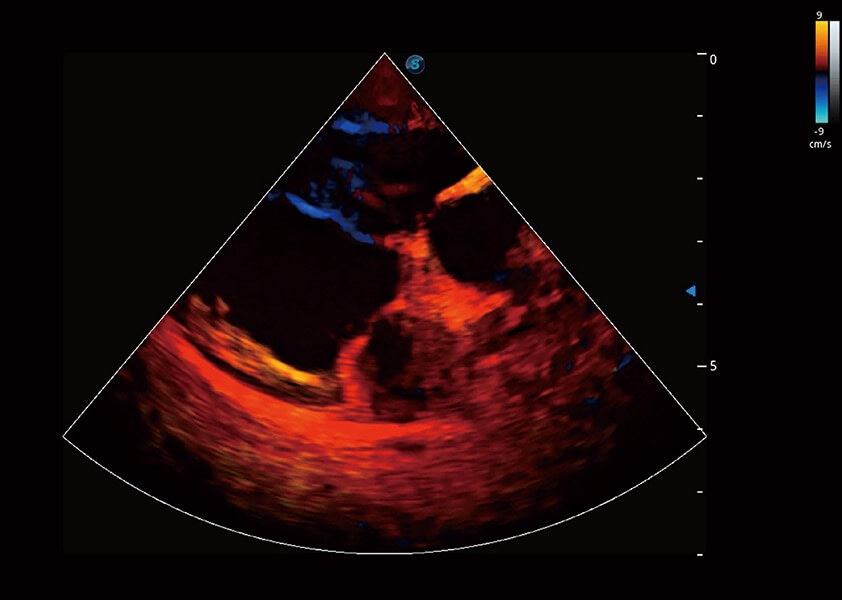

ProPet 60 作为一款高端台式动物超声设备,为动物医生的日常诊断提供了一系列贴合动物临床需求、解决临床实际问题的高级成像功能。凭借全系列高清探头,满足医生对腹部、心脏、生殖、浅表、肌骨等成像的所有需求,切实帮助您提升检查效率,提高诊断信心。

兽用彩色多普勒超声诊断系统

动物是人类最亲密的朋友和最值得信赖的伙伴。乐玩lewin国际也一直致力于探索动物专用的超声影像解决方案。 全新推出的ProPet系列,是乐玩lewin国际在动物超声影像智能化、专业化、精准化的一次跨越式革新。动物不能用言语来表述自己的不适,通过超声影像,ProPet系列搭建了动物医生与不同物种沟通的“桥梁”,为动物医生注入了“治愈之力”。